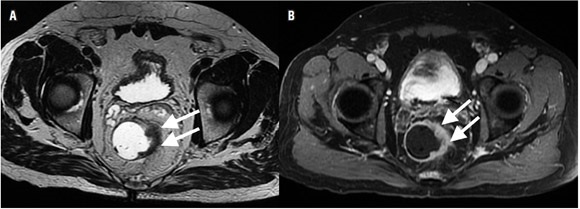

El tamaño de los ganglios linfáticos es un dato de valor limitado para determinar la presencia de metástasis (8,15). Se debe tener en cuenta que hay micrometástasis en ganglios de tamaño normal (5,43,44). Un diámetro de 5 mm tiene una sensibilidad de 68% y una especificidad de 78% para diferenciar ganglios malignos de benignos (8,10,15,45). Este valor no es relevante en el cáncer de recto, ya que entre el 30% al 50% de los ganglios linfáticos con metástasis ocurren en ganglios menores de 5 mm (15,46,47); por lo tanto, la morfología del ganglio linfático, incluyendo los márgenes o contornos y características internas (homogeneidad), son el punto clave para determinar metástasis (8,10,48-51). Un ganglio de aspecto metastásico presenta márgenes espiculados y contenido heterogéneo (15). Las calcificaciones en el interior del ganglio son sugestivas de malignidad (8). A pesar de esto, el problema de basarse en la morfología es que en los ganglios de mayor tamaño no es posible diferenciar entre ganglios neoplásicos o reactivos, y en los ganglios de menor tamaño pueden no identificarse las micrometástasis (figura 7A) (18). Cabe anotar que la sensibilidad de la resonancia magnética reportada en la literatura para la detección de ganglios linfáticos varía entre el 39% al 95% (5-7,22,52,53,54,55).

Se ha usado medio de contraste (gadolinio) para la valoración de los ganglios linfáticos con estudios que reportan una precisión de hasta 70% (figura 7B) (5,8). Heriot y colaboradores reportan una sensibilidad y especificidad superiores al 80% para la detección de compromiso ganglionar cuando se usan antenas intrarrectales (22,56).